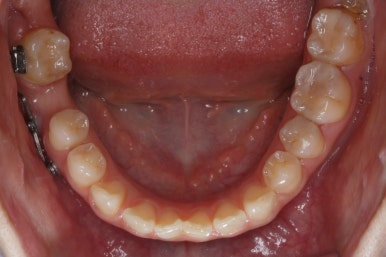

초진 때의 입안 모습입니다.

앞니는 고른 편이였으나 군데군데 틈새가 있었습니다. 약간 삐뚠 모습도 보이지만 환자분께서 개선을 하고자 했던 부분은 아래쪽 어금니 1개가 없는 자리였습니다.